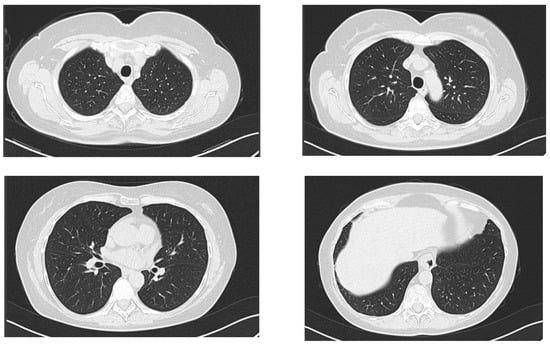

2.1. Case Report 1